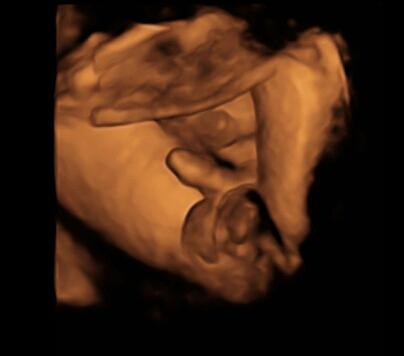

was für ein Käse! gut, in der 20. ssw bei einem Mädel wäre ich auch noch vorsichtig, aber es gibt auch ganz sichere vorgeburtliche outings. und wenn mein Sohn nach dem Foto ein Mädel gewesen wäre, hätte ich einen gentest gemacht um zu beweisen das er vertauscht wurde....

Bild zu